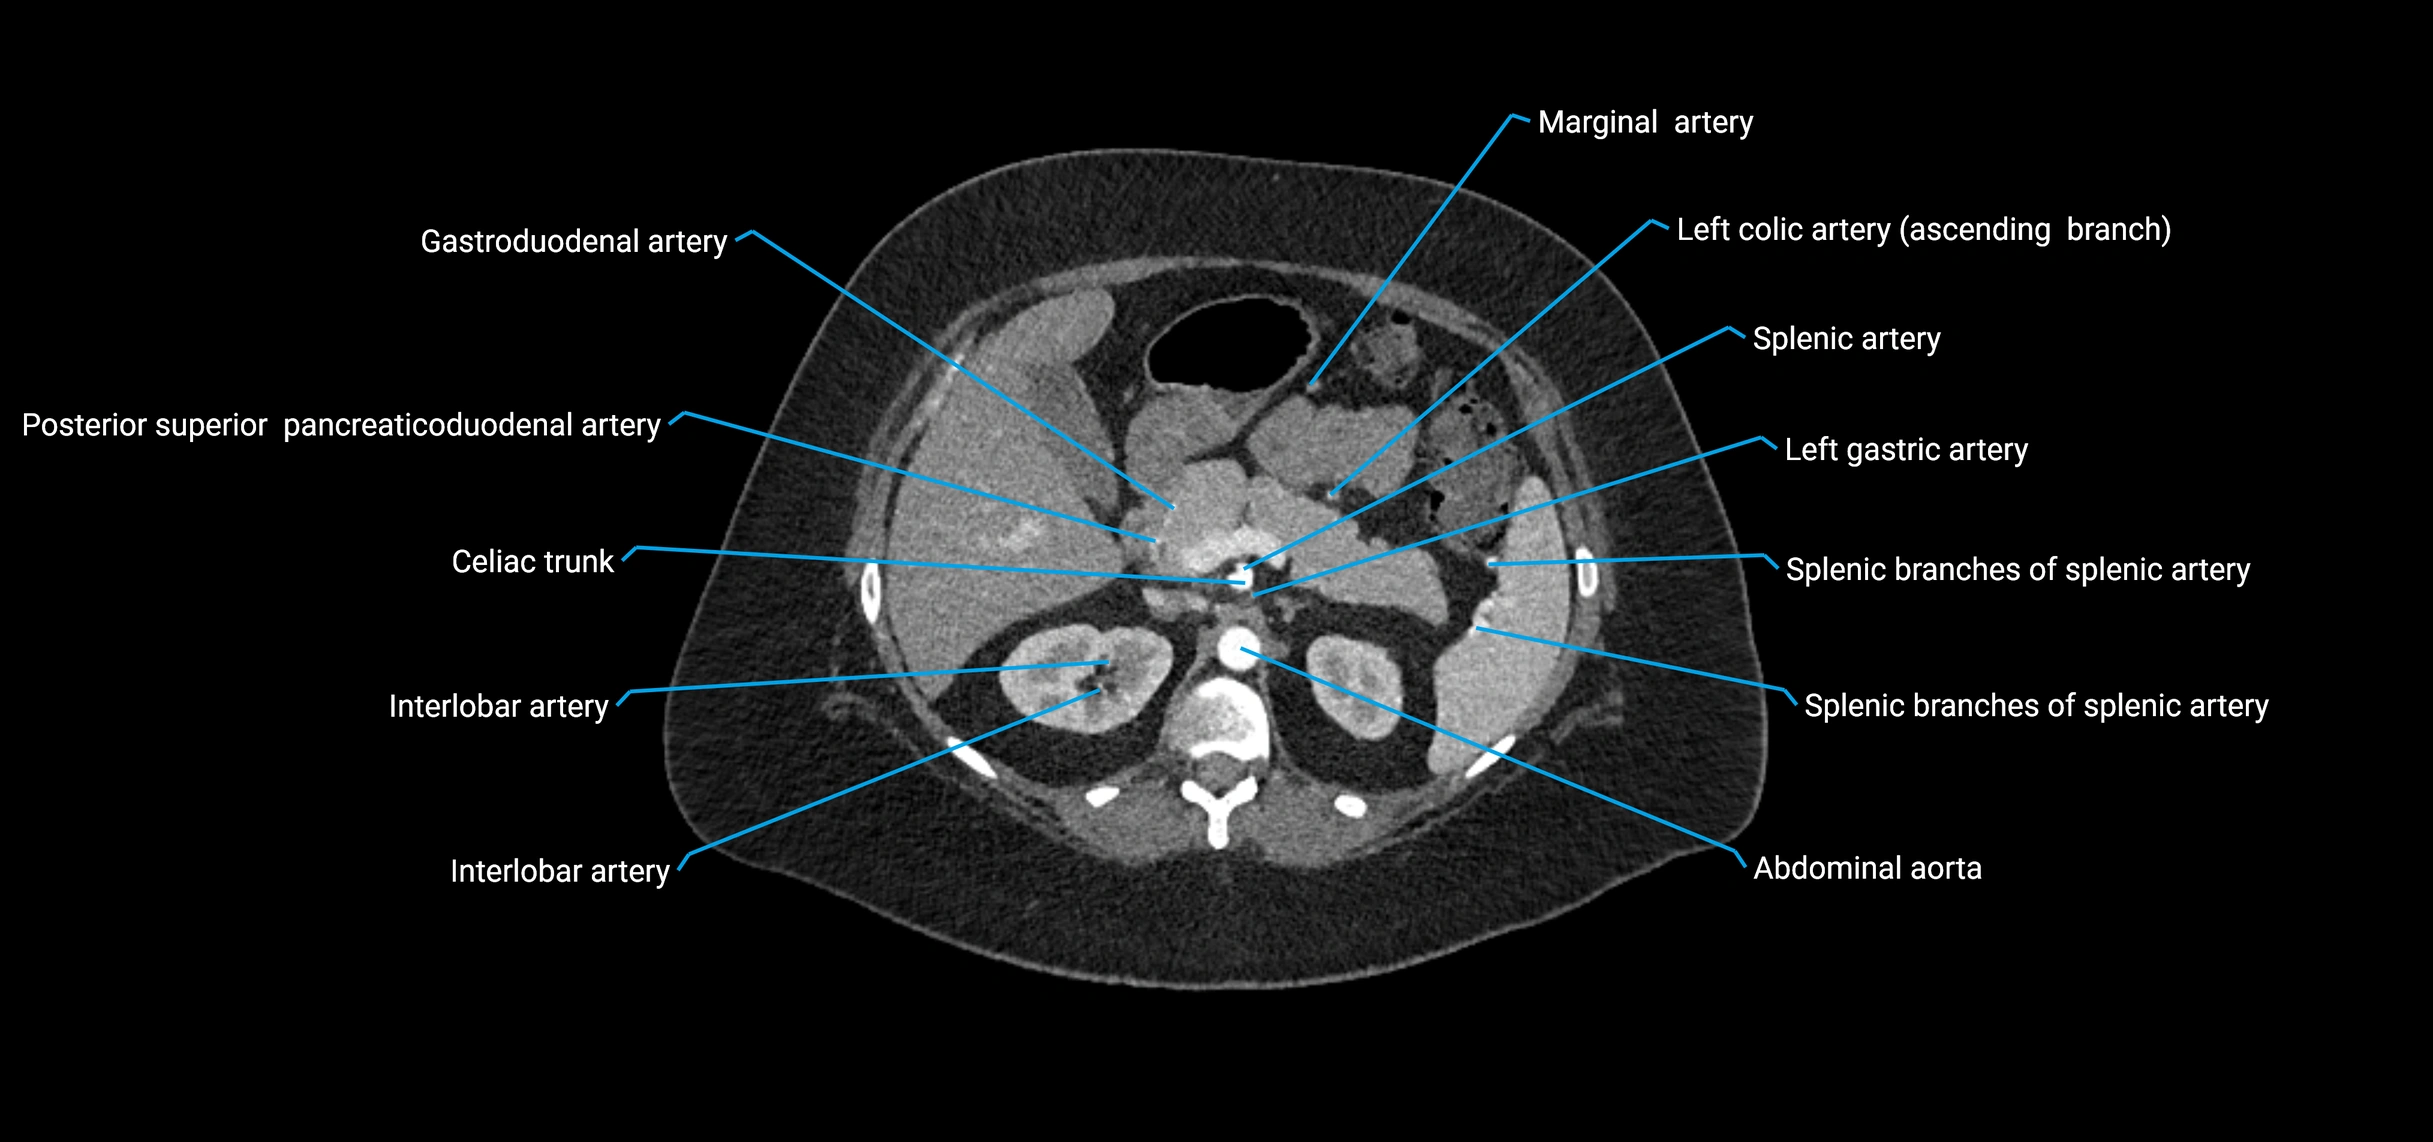

Branches

• Unpaired visceral branches: celiac trunk, superior mesenteric artery (SMA), inferior mesenteric artery (IMA)

• Paired visceral branches: middle suprarenal arteries, renal arteries, gonadal arteries (testicular or ovarian)

CT Appearance

Contrast-enhanced CT (CTA):

• Gold standard for abdominal aortic imaging

• Provides excellent detail of lumen, wall, aneurysm, thrombus, and branch vessels

• Multiplanar and 3D reconstructions help in aneurysm measurement, stent graft planning, and dissection evaluation

CT images

image